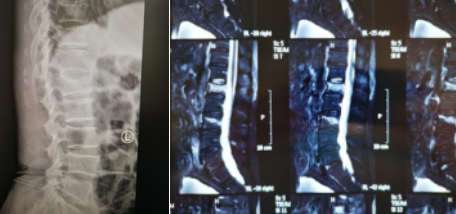

74岁老人骑电动车,被驶过的大货蹭倒,摔成腰1、腰3椎体压缩性骨折,接诊的betway在线登陆采用天玑骨科机器人精准“操刀”,为患者进行了椎体成形手术,24小时后老人已经下地活动,手术获得成功。

患者李大爷,家住丰县,被送到必威官方首页官网betway时,由脊柱科孟磊副主任医师接诊,老人腰1、腰3椎体压缩性骨折,这种压缩性骨折是无法通过普通的卧床静养就能自行恢复的,需要做椎体成形手术,脊柱科尚军主任和手术小组讨论后,决定采用骨科机器人辅助手术。

第二天,孟磊副主任医师、孙玉龙医师手术团队为患者进行了机器人辅助下腰1腰3椎体成形术。

术前设计

手术过程中,孟磊副主任医师在骨科机器人的帮助下,精确定位后,在患者后腰部开了一个直径0.5厘米的小孔,手术器械由此进入,先为患者进行腰椎复位,随后,医生在复位腰椎内注入“骨水泥”,完成治疗。